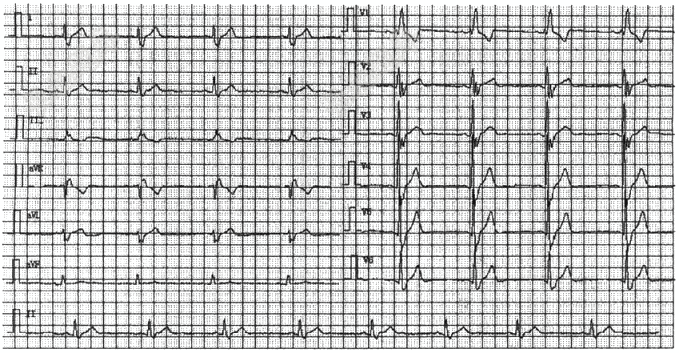

- 单项选择题下列心电图检查最可能的是( )

A、左前分支阻滞

B、左后分支阻滞

C、完全性左束支阻滞

D、不完全性右束支阻滞

E、完全性右束支阻滞